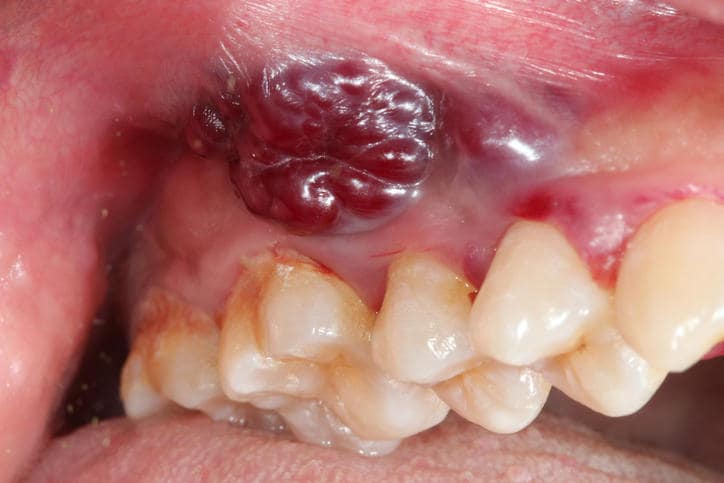

- melanomi maligni orali (quando il cancro inizia nei melanociti, le cellule che producono il pigmento della pelle; appaiono come gonfiori scuri e screziati che spesso sanguinano),

Il tumore in bocca coinvolge di norma le labbra o la lingua; può apparire come un nodulo od un’ulcera che può presentarsi come:

- una profonda ulcerazione con contorni netti,

- pallida, scura o scolorita,

- una formazione indolore in una prima fase, per poi causare una sensazione di bruciore o fastidio quando il tumore è avanzato.